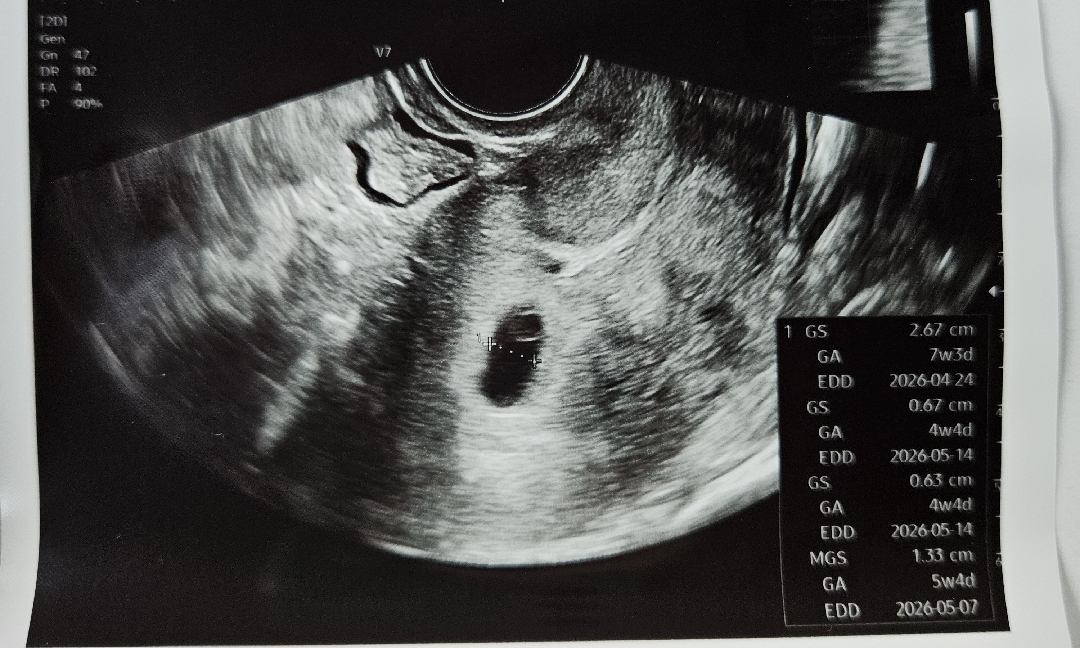

난황이 크대요

병원에 가서 초음파 보고왔어요 5주 4일차 아기집과 난황이 보였는데 난황크기가 크다고 다음주에 다시 봐야할것 같다고 하시네요 이런경우 유산확률이 좀 높은가봐요 지금 입덧도 너무 심한데 힘들긴 힘들거든요 하지만 잘 참아볼 수 있으니까 ㅠㅠ 제발 아니었으면 좋겠어요!!

저도 난황이 엄청 큰것 까지는 모르겠눈데 ㅠㅠ 혹시 아기집 사이즈에 비해서 크다고 하신건가요..??

난황크기 큰거 맞나요..?